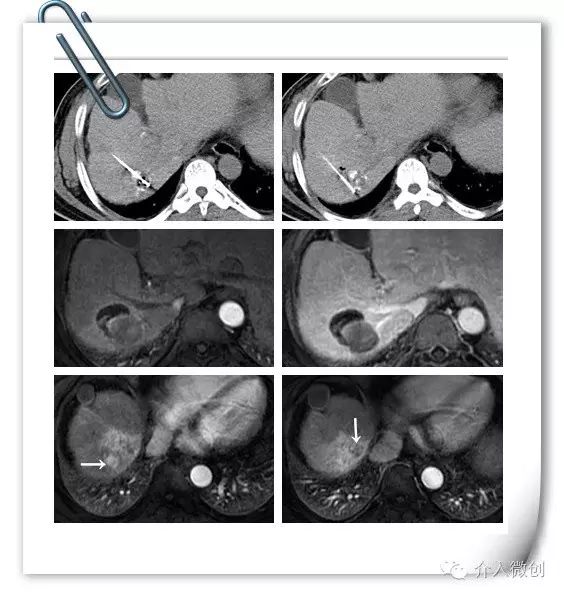

中年男性,诊断为原发性肝癌并门脉右支癌栓,术前甲胎蛋白升高(AFP:484ug/ml)。先予以行肝动脉化疗栓塞术(TACE),术后复查CT提示肝内病灶部分碘油沉积,门脉右支癌栓亦可见碘油沉积。

术前术后影像对比

针对病灶碘油沉积欠缺情况,予以行CT引导下射频消融,治疗后病灶中心出现气化。

射频消融治疗

射频消融后1个月复查MRI提示病灶完全消融,边缘可见胆汁瘤,患者无发热、黄疸等不适。但近膈顶部可见2个小结节新发病灶,甲胎蛋白(AFP:244ug/ml)亦未明显下降。

针对新情况,为该患者制定治疗计划:肝动脉化疗栓塞术+射频消融术控制肝内新发瘤灶,并联合碘125放射性粒子植入控制门脉右支癌栓。

CT引导下肝癌射频消融术+门脉癌栓放射性粒子植入术,术后2周复查肝脏MRI提示肝内病灶得到有效控制,甲胎蛋白(AFP:14 ug/ml)亦明显下降,术后1个月甲胎蛋白降至正常范围(AFP:3.9 ug/ml)。

射频消融+放射性粒子植入